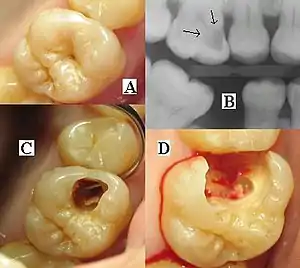

![]() | |

| Destruction of a tooth by dental caries and disease | |